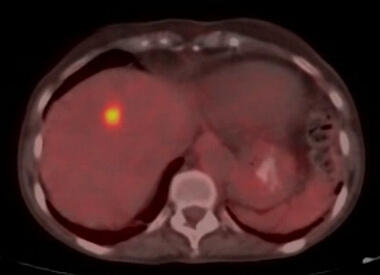

This is a PET-CT image demonstrating a metastatic tumor in the right lobe of the liver.